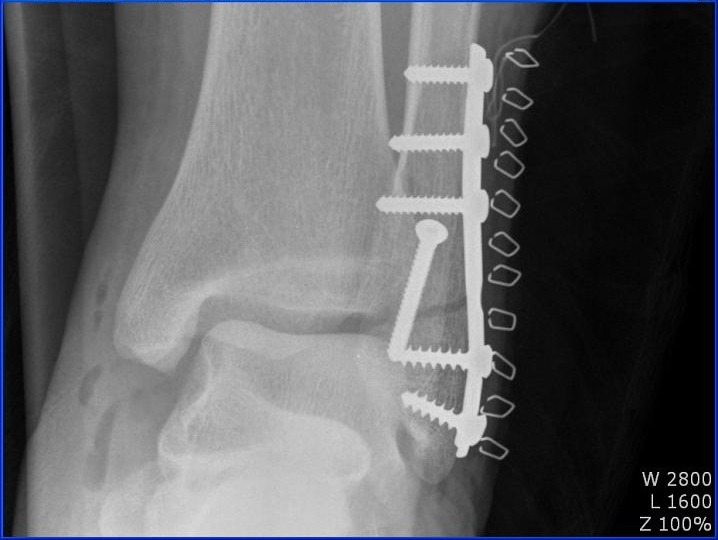

<11월 9일> 수술

- 외과 골절 및 내외측 인대파열이라는 진단을 받았는데 골절부분만 수술